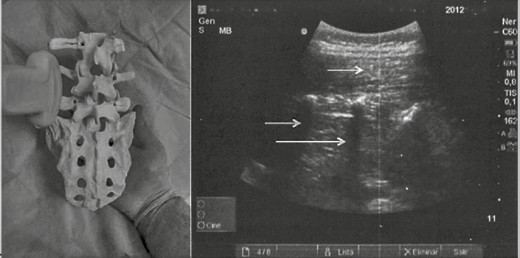

La medición será realizada con el botón de medida o caliper del ecógrafo que está integrado en la botonería su función será importante ya que nos ayuda a medir las proporciones de las estructuras que estamos estudiando o las velocidades de la sangre en los estudios vasculares. O puede también estar ubicado el calipre en la pantalla. Entonces medimos la distancia de la piel hasta la porción anterior del complejo ligamento amarillo-duramadre q será el límite inferior de la profundidad intratecal o una aproximación de la profundidad del espacio epidural 12, 9. Esta sería una medición del espacio epidural. Siendo esta una medición indirecta del espacio o profundidad intratecal. Esto en plano o abordaje transversal y el paramediano longitudinal como herramienta complementaria ( Figura 4).

Fuente:Carrillo- Esper R y cols. Ultrasonografía del espacio epidural lumbar Vol.40, N°2, 2017